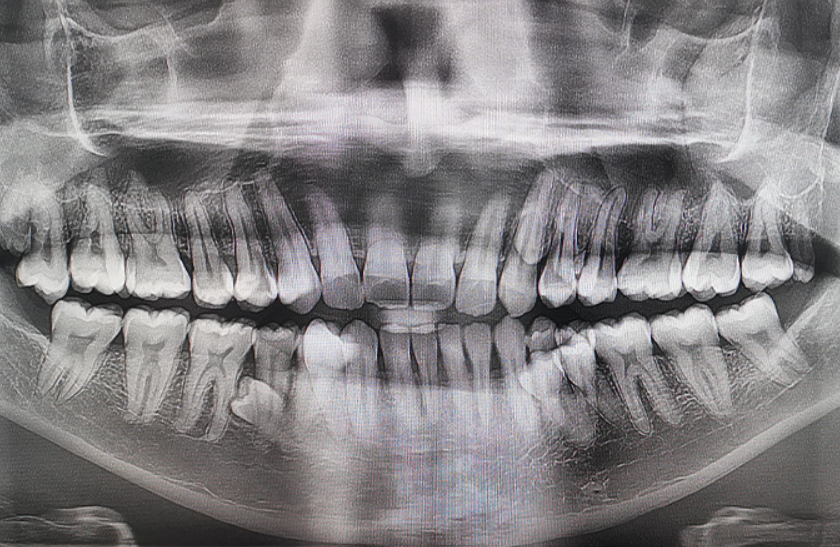

Prathab Muniandy is a Malaysian dad who has been making headlines with a world record and a smile packed with more teeth than anyone thought possible.This 33-year-old engineer in the oil and gas industry holds the Guinness World Record for the most teeth in a person's mouth (male), with a stunning total of 42 erupted teeth, 10 more than the average 32. His achievement was officially verified on December 28, 2023, in Klang, Selangor, after exams by two dentists confirmed it, along with two additional unerupted ones, according to Guinness World Records.

Prathab first spotted his extra chompers casually during a 2021 family tea gathering. According to Guinness World Records reports, he mentioned it to relatives, and they counted 38 teeth right then. A dental X-ray revealed four more waiting to emerge, and by early 2023, the full 42 had arrived, mostly straight.He shared to GWR, “I first noticed this in 2021 during a family tea-time gathering, when I mentioned to my family that I seemed to have extra teeth growing.

We counted them together and found that I had 38 teeth at the time. A dental X-ray later showed that there were four more teeth that had yet to erupt. By early 2023, I realized that I had a total of 42 teeth. Fortunately, most of the teeth grew straight and without any complications”.